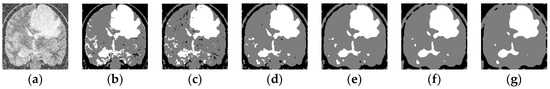

4.2.4. Medical Images

| Image | Algorithm | Acc | Sen | Jaccard | PSNR | SA | Kappa | mIoU | DICE |

|---|---|---|---|---|---|---|---|---|---|

| Tr-me_ 0180 + RN(80) | ARFCM | 0.8089 | 0.7134 | 0.5544 | 11.0986 | 0.7134 | 0.5777 | 18.481 | 0.7134 |

| KWHLICM | 0.9494 | 0.9241 | 0.8589 | 17.1511 | 0.9241 | 0.8782 | 28.6309 | 0.9241 | |